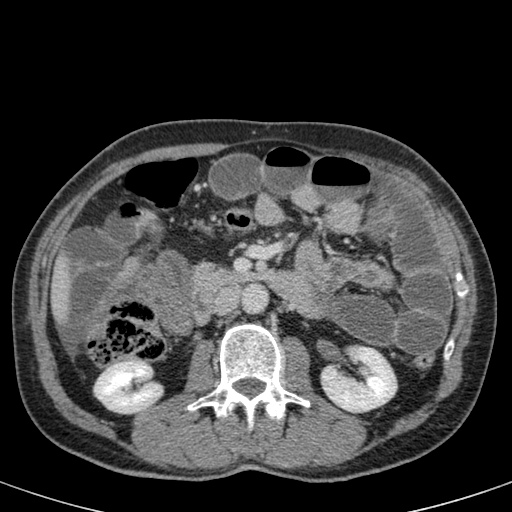

Ca lâm sàng bên trái cho thấy một bệnh nhân khác bị tắc ruột dạng quai kín.

Mặc dù các mạch máu ngấm thuốc tốt, nhưng dường như thành ruột không ngấm thuốc.

Các dấu hiệu thiếu máu cục bộ khác trong ca này bao gồm phù nề mạc treo và dày thành ruột.

Ruột bị nhồi máu được phát hiện trong quá trình phẫu thuật.

Nếu quai kín dài hơn và định hướng vuông góc với mặt phẳng cắt, chúng ta sẽ thấy một cụm quai ruột như trong ca lâm sàng bên trái.

Đôi khi điều này khó nhận biết chỉ trên các lát cắt ngang và các tái tạo mặt phẳng coronal hoặc sagittal có thể hữu ích.

Trong ca này, cũng có phù nề mạc treo và cổ